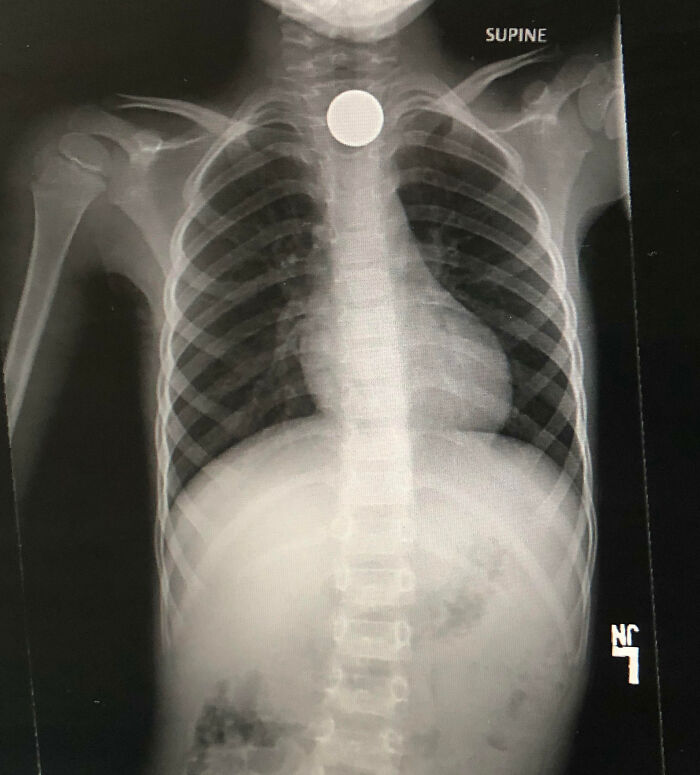

23.아들이 니켈 하나를 삼키고 0.05달러를 4400달러로 바꾸기로 결심했다.